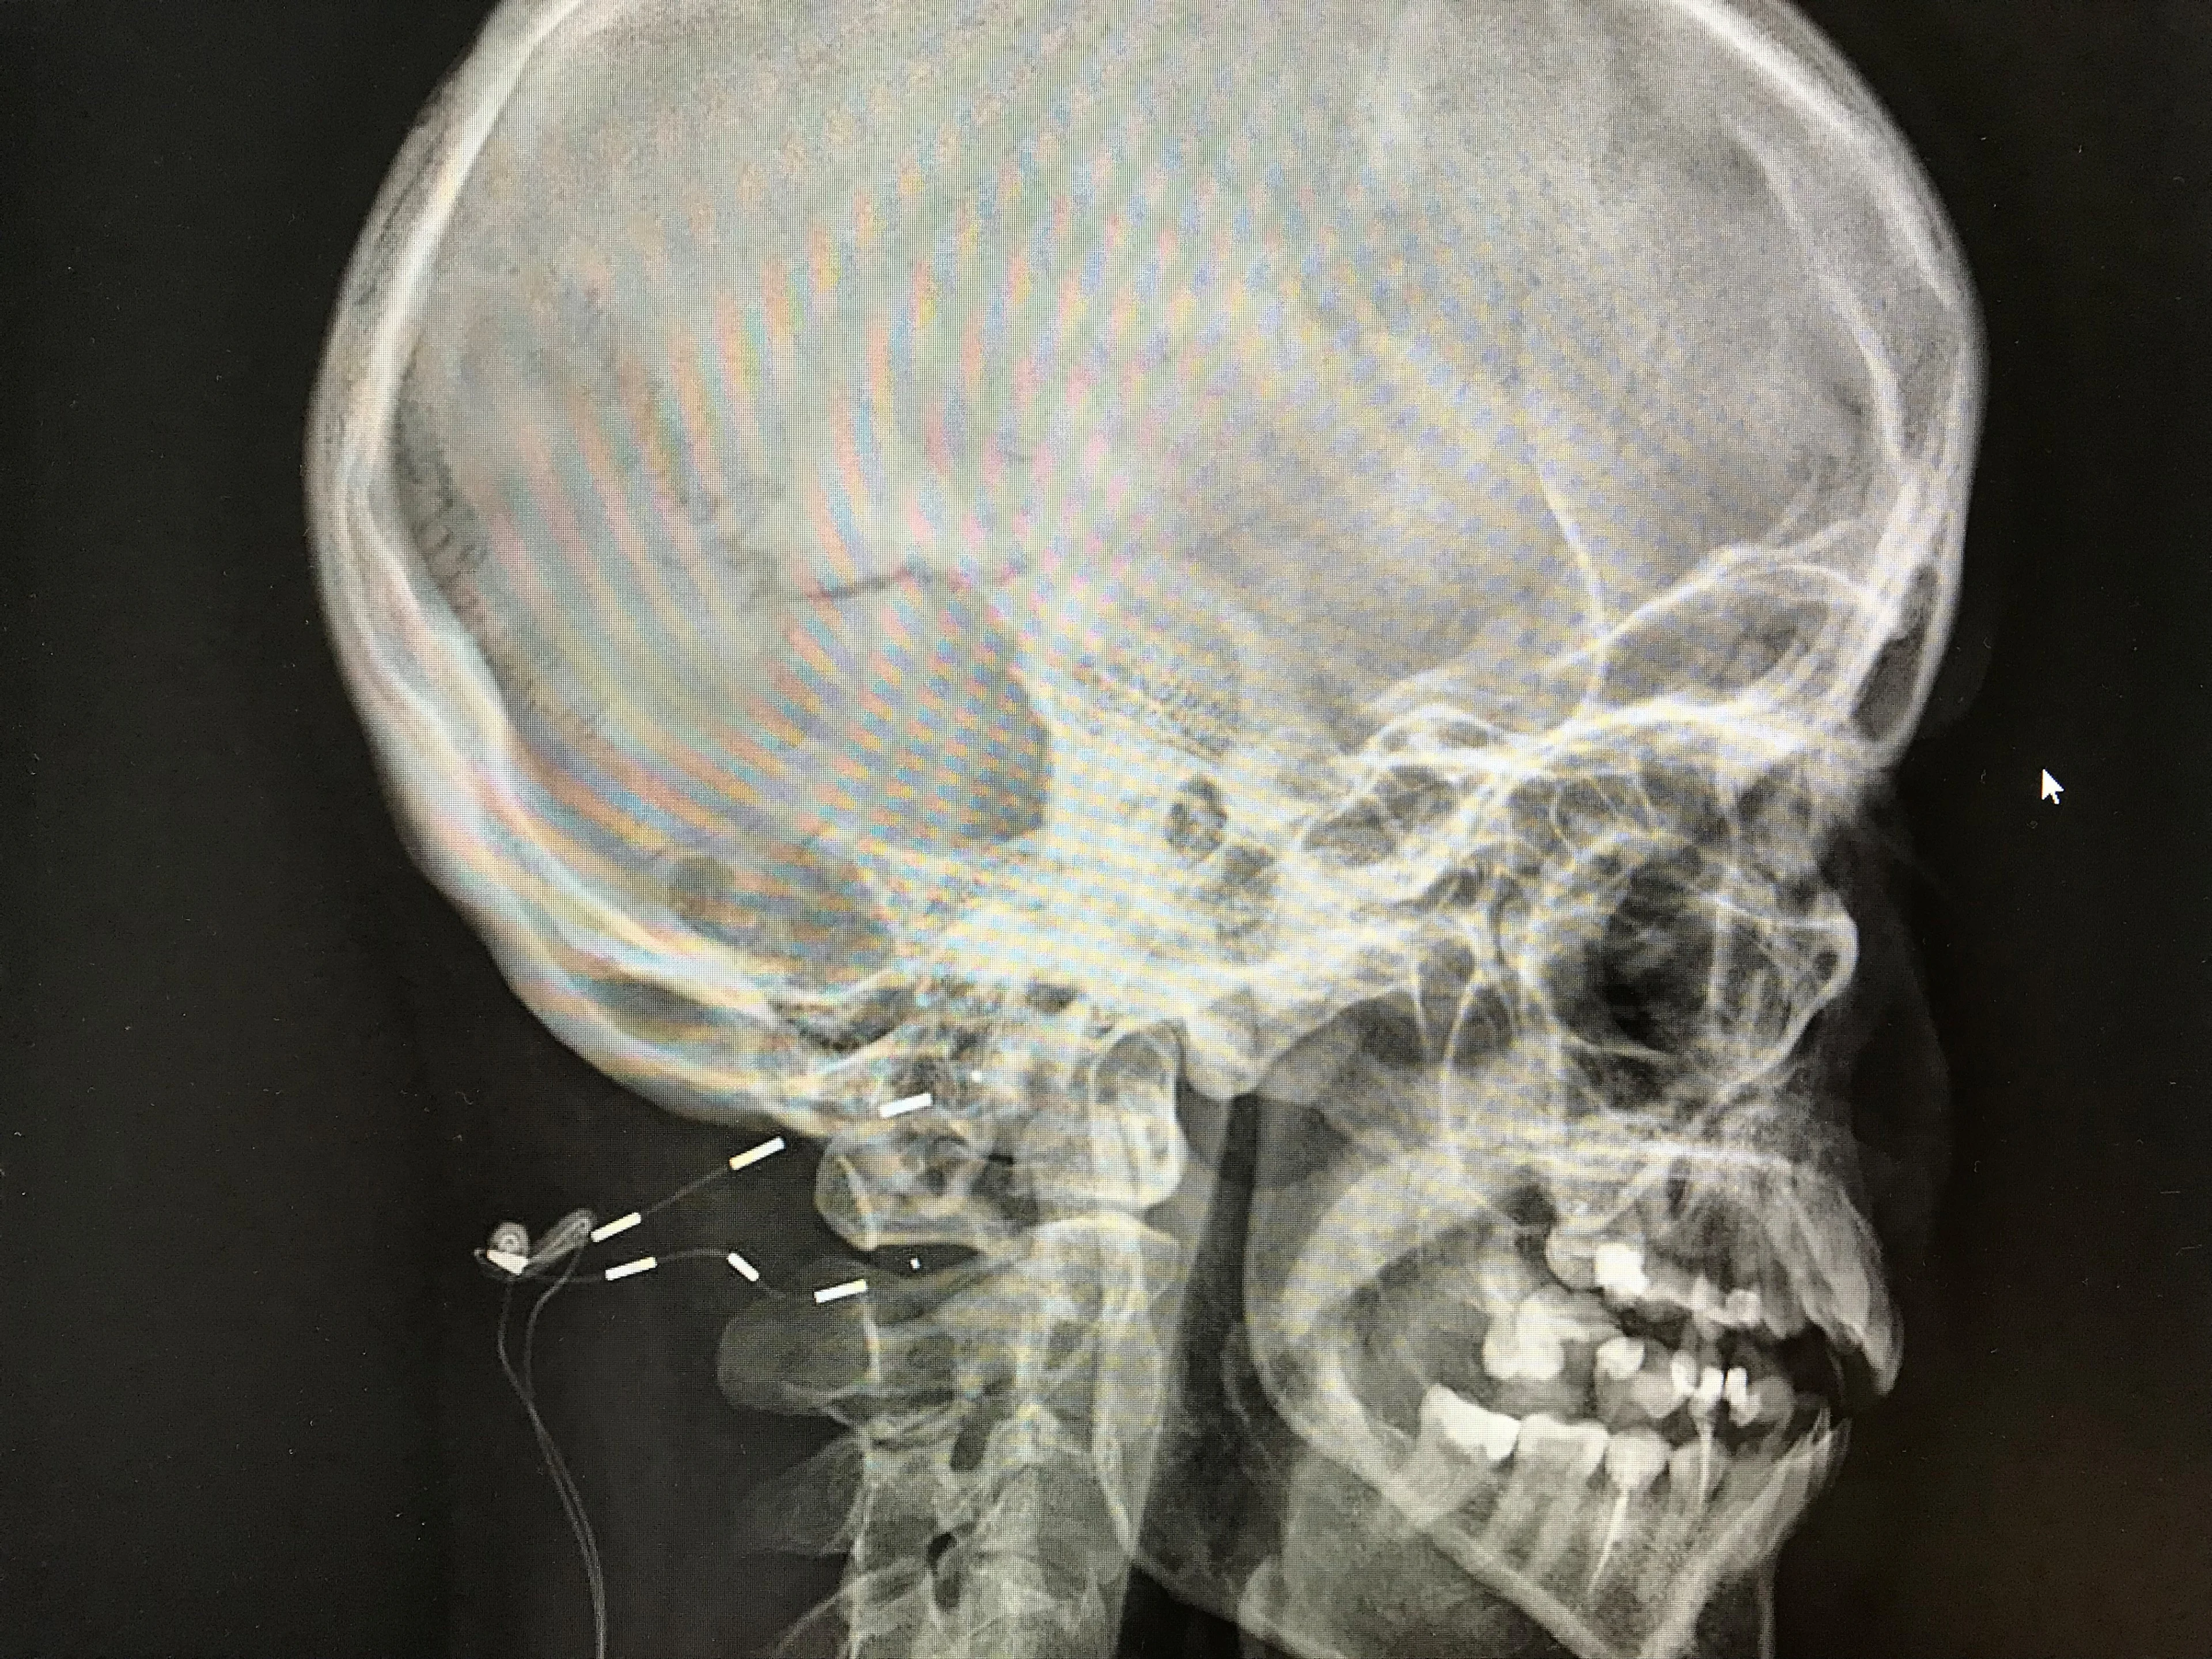

Het prikkelen van de achterhoofdzenuw met stroomstootjes kan de aanvallen voorkomen, zo ontdekte het Leids Universitair Medisch Centrum (LUMC) tijdens een onderzoek. Patiënten krijgen onderhuids een zogeheten neurostimulator geïmplanteerd. Het apparaat geeft kleine stroomstootjes af waarmee de pijnsignalen naar de hersenen worden verstoord.